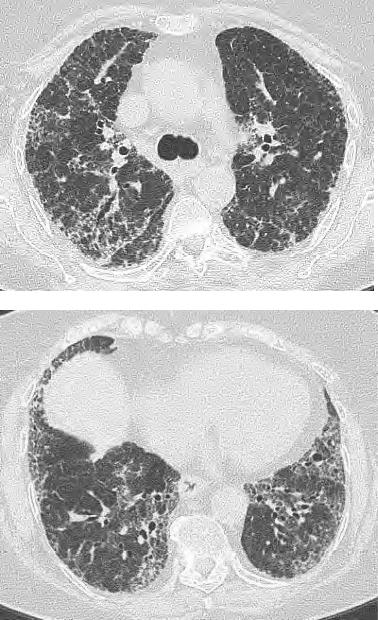

КТ-паттерн, неопределенный для ОИП

Распределение

Вариабельное или диффузное

КТ признаки

наличие фиброза с некоторыми чертами, характерными для паттерна «не-ОИП»

КТ-паттерн более характерный для диагноза «не-ИЛФ»

Фиброз с преобладанием в верхних

Любое из следующих:

и средних отделах

Преобладающая консолидация

Перибронховаскулярное

Протяженные поля чистого матового

предоминирование с сохранением

стекла (без обострения)

субплевральных отделов

Выраженное мозаичное уплотнение с

четкими признаками лобулярных

воздушных ловушек во время выдоха

Диффузные узелки или кисты

Lynch D et al. Lancet Respir Med 2017; http://dx.doi.org/10.1016/S2213-2600(17)30433-2

Мозаичное уплотнение

Профузные изменения по типу ‘чистого’

матового стекла

Узелки

Бронхоцентричность